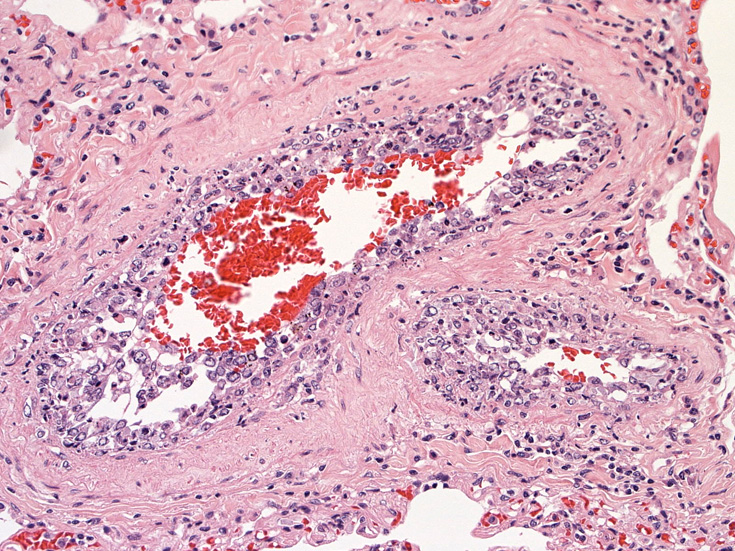

脳;くも膜下腔の小動脈内, 脳白質の細血管内に腫瘍細胞が充満している。

肺A;肺胞壁が厚くなり毛細血管内に腫瘍細胞が多数出現している(A).

肺B;小気管支動脈, 肺動脈内を腫瘍細胞が閉塞する. 動脈内膜に浸潤性増殖している(B)。